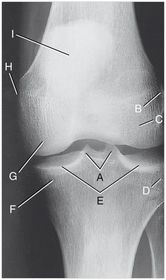

A. medial and lateral intercondylar tubercles B. lateral epicondyle femur C. lateral condyle femur D. lateral condyle tibia E. articular facets tibia (tibial plateau) F. medial condyle tibia G. medial condyle femur H. medial epicondyle femur I. patella